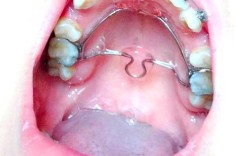

• 正畸 欧米茄曲图片

正畸 欧米茄曲图片

正畸治疗中,欧米茄曲(OmegaLoop)作为一种关键的弓丝弯制附件,在牙齿移动控制、间隙管理及稳定维持中发挥着不可替代的作用,其独特的Ω形结构设计,既能为牙齿提供持续轻柔的矫治力,又能作为“停止曲”限制牙齿移动范围,是正畸医生精准调控牙...